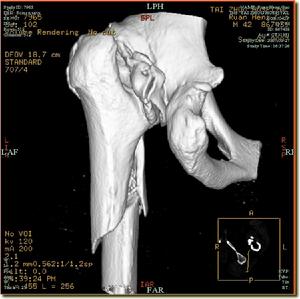

在有條件時可套用CT或MRI檢查便可明確診斷。

2.股骨頭 新生兒的股骨頭為畸形,表面有光滑的軟骨面,而後由於脫位於髖臼外,股骨頭的形狀可逐步改變,頭可變大或變小,呈尖錐形或葺形,股骨頭受壓處往往出現部分股骨頭扁平。股骨頭骨骺出現遲緩。有時套用強大暴力手術復位,由於髖臼與股骨頭不相適應,對股骨頭的壓力過大,可造成股骨頭無菌性壞死。

3.股骨頸 由於髖關節脫位,股骨頸一般變短而粗,是肢體縮短的一個原因。股骨頸前傾角變大,據Caffey報導正常新生兒前傾角為25°,以後逐步減少至5°~15°之間,當股骨頭外移後,由於正常肌力作用,向股骨頭向前鏇轉,前傾角因而增大,一般在60°~90°之間。如果能早期復位,前傾角多能逐步自行糾正。尤其在1歲以內得到復位者幾乎都能恢復正常。

2.關節囊 正常的髖關節囊是一層纖維組織0.5~1.0mm厚薄。自從股骨頭脫離髖臼向外向上移位,小孩負重後,關節囊受到牽拉而增長增厚有時可大2~3mm之多,長期牽拉使關節囊與髖臼上方髂翼粘連,加上圓韌帶、盤狀軟骨與關節囊之間粘連,形成整整一片結締組織,阻礙股骨頭進入髖臼。關節囊在後期呈葫蘆形,有狹窄的頸部,股骨頭本身就不能通過。髂腰肌腱經過關節囊前面,有時在很早期出現一個切跡,阻礙股骨頭復位。關節囊附著在股骨頭以下而不是附著大小粗隆之間。